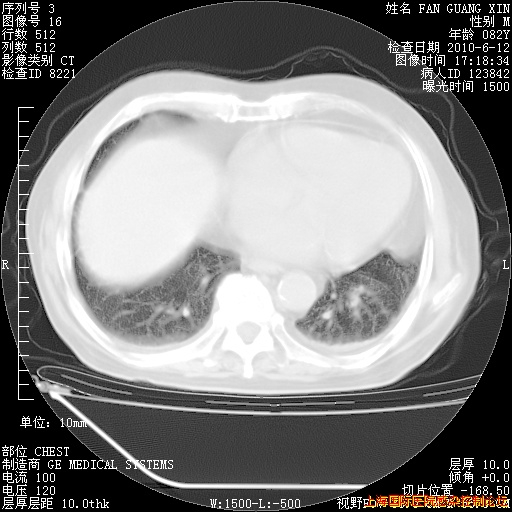

6月12日肺窗

整整相隔30天的肺部CT好像有所好转啊。甲强龙减量第3天,需要观察体温。

海管,自昨日你和我通完话后,不知您岳父消化道症状有无缓解?体温怎样?阅读7.12日胸部ct,个人认为目前激素治疗是有效的,甲强龙减量是适宜的。因在抗痨治疗,需密切观察肝功、肾功能和血常规。不过,老年、长期住院和大量使用激素,很担心菌群失调发生